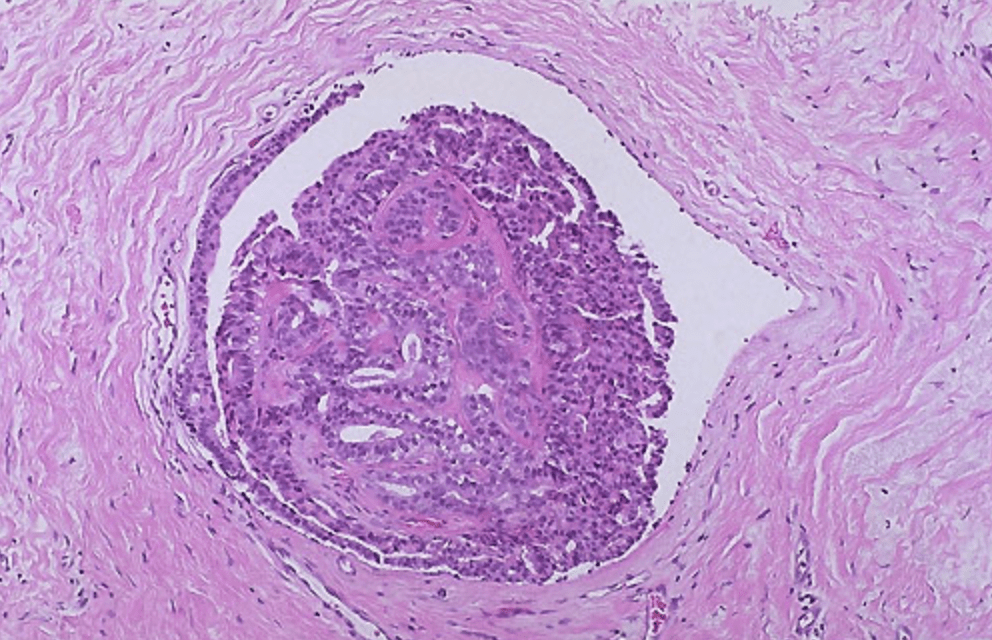

Intraductal Papilloma with Atypia

- Although a solitary intraductal papilloma is benign:

- When a papillary lesion with atypia is identified on core biopsy:

- Surgical excisional biopsy is recommended to rule out an associated in situ or invasive cancer:

- Studies have demonstrated an upstage rate of 22% to 67% when atypia is present:

- But only 3%to 9% in the absence of atypia